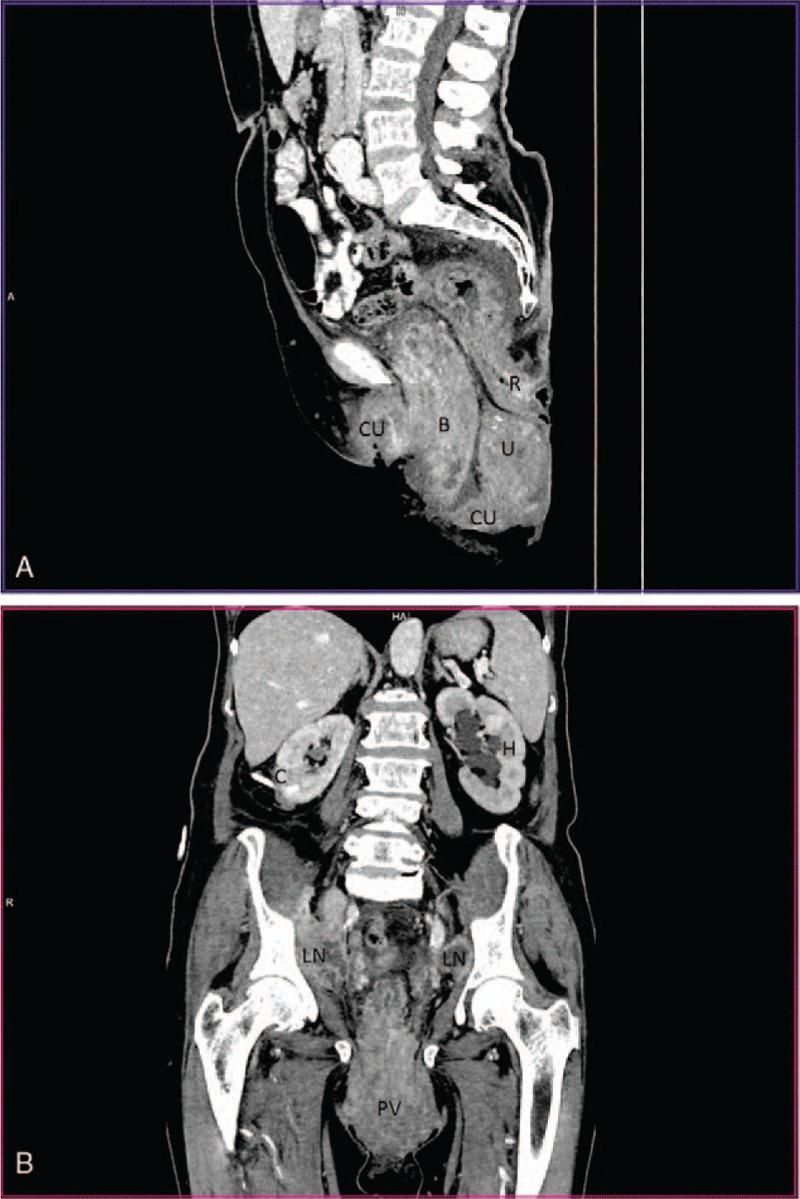

Primary vaginal squamous cell carcinoma (SCC) is a rare disease. Primary SCC in prolapsed vagina is extremely rare. In the presented case additional bladder involvement was found.

Diagnosis was confirmed by the vaginal ulceration biopsy and cystoscopic biopsy of the involved bladder.

In the case presented percutaneous nephrostomy was the only possible treatment of hydronephrosis.

原发性阴道鳞状细胞癌(SCC)是一种罕见疾病。脱垂阴道中的原发性SCC极为罕见。在本病例中,发现了额外的膀胱受累情况。

通过阴道溃疡活检和受累膀胱的膀胱镜活检确诊。

在本病例中,经皮肾造瘘术是肾积水的唯一可能治疗方法。